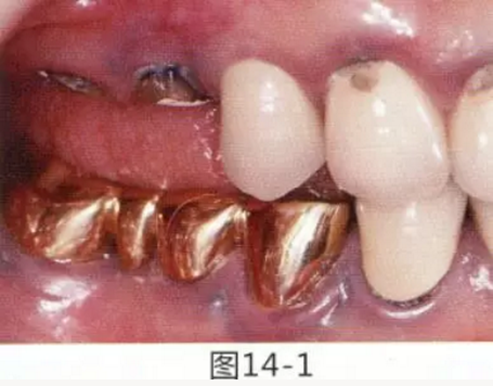

圖14-1 修復體周圍角化牙齦較少,很難進行清潔的狀態(tài),并有緣下齲壞的發(fā)生。

圖14-2,3 徹底去除齲壞后,試圖通過游離齦移植獲取生物學寬度和附著齦。

圖14-4~6修復體周圍角化牙齦較少,很難進行清潔的狀態(tài),并有緣下齲壞的發(fā)生。

圖14-7 配戴最終修復體完成5年后的狀態(tài)。保持良好。